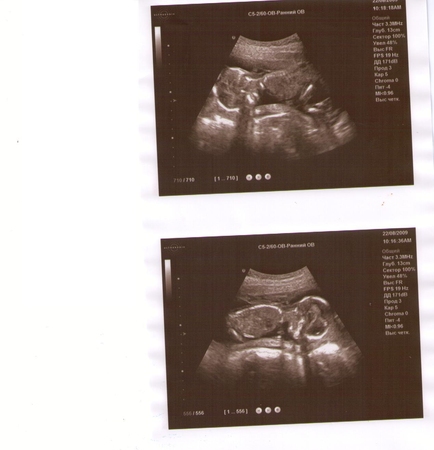

А вот наше фото с узи, 17 недель и 2 дня

Попочка уже не помещается в фото..большие уже стали!))) Но как свазала врач, будем не высокими..да и куда уж нам, я метр с кепкой и муж..полтора)))))